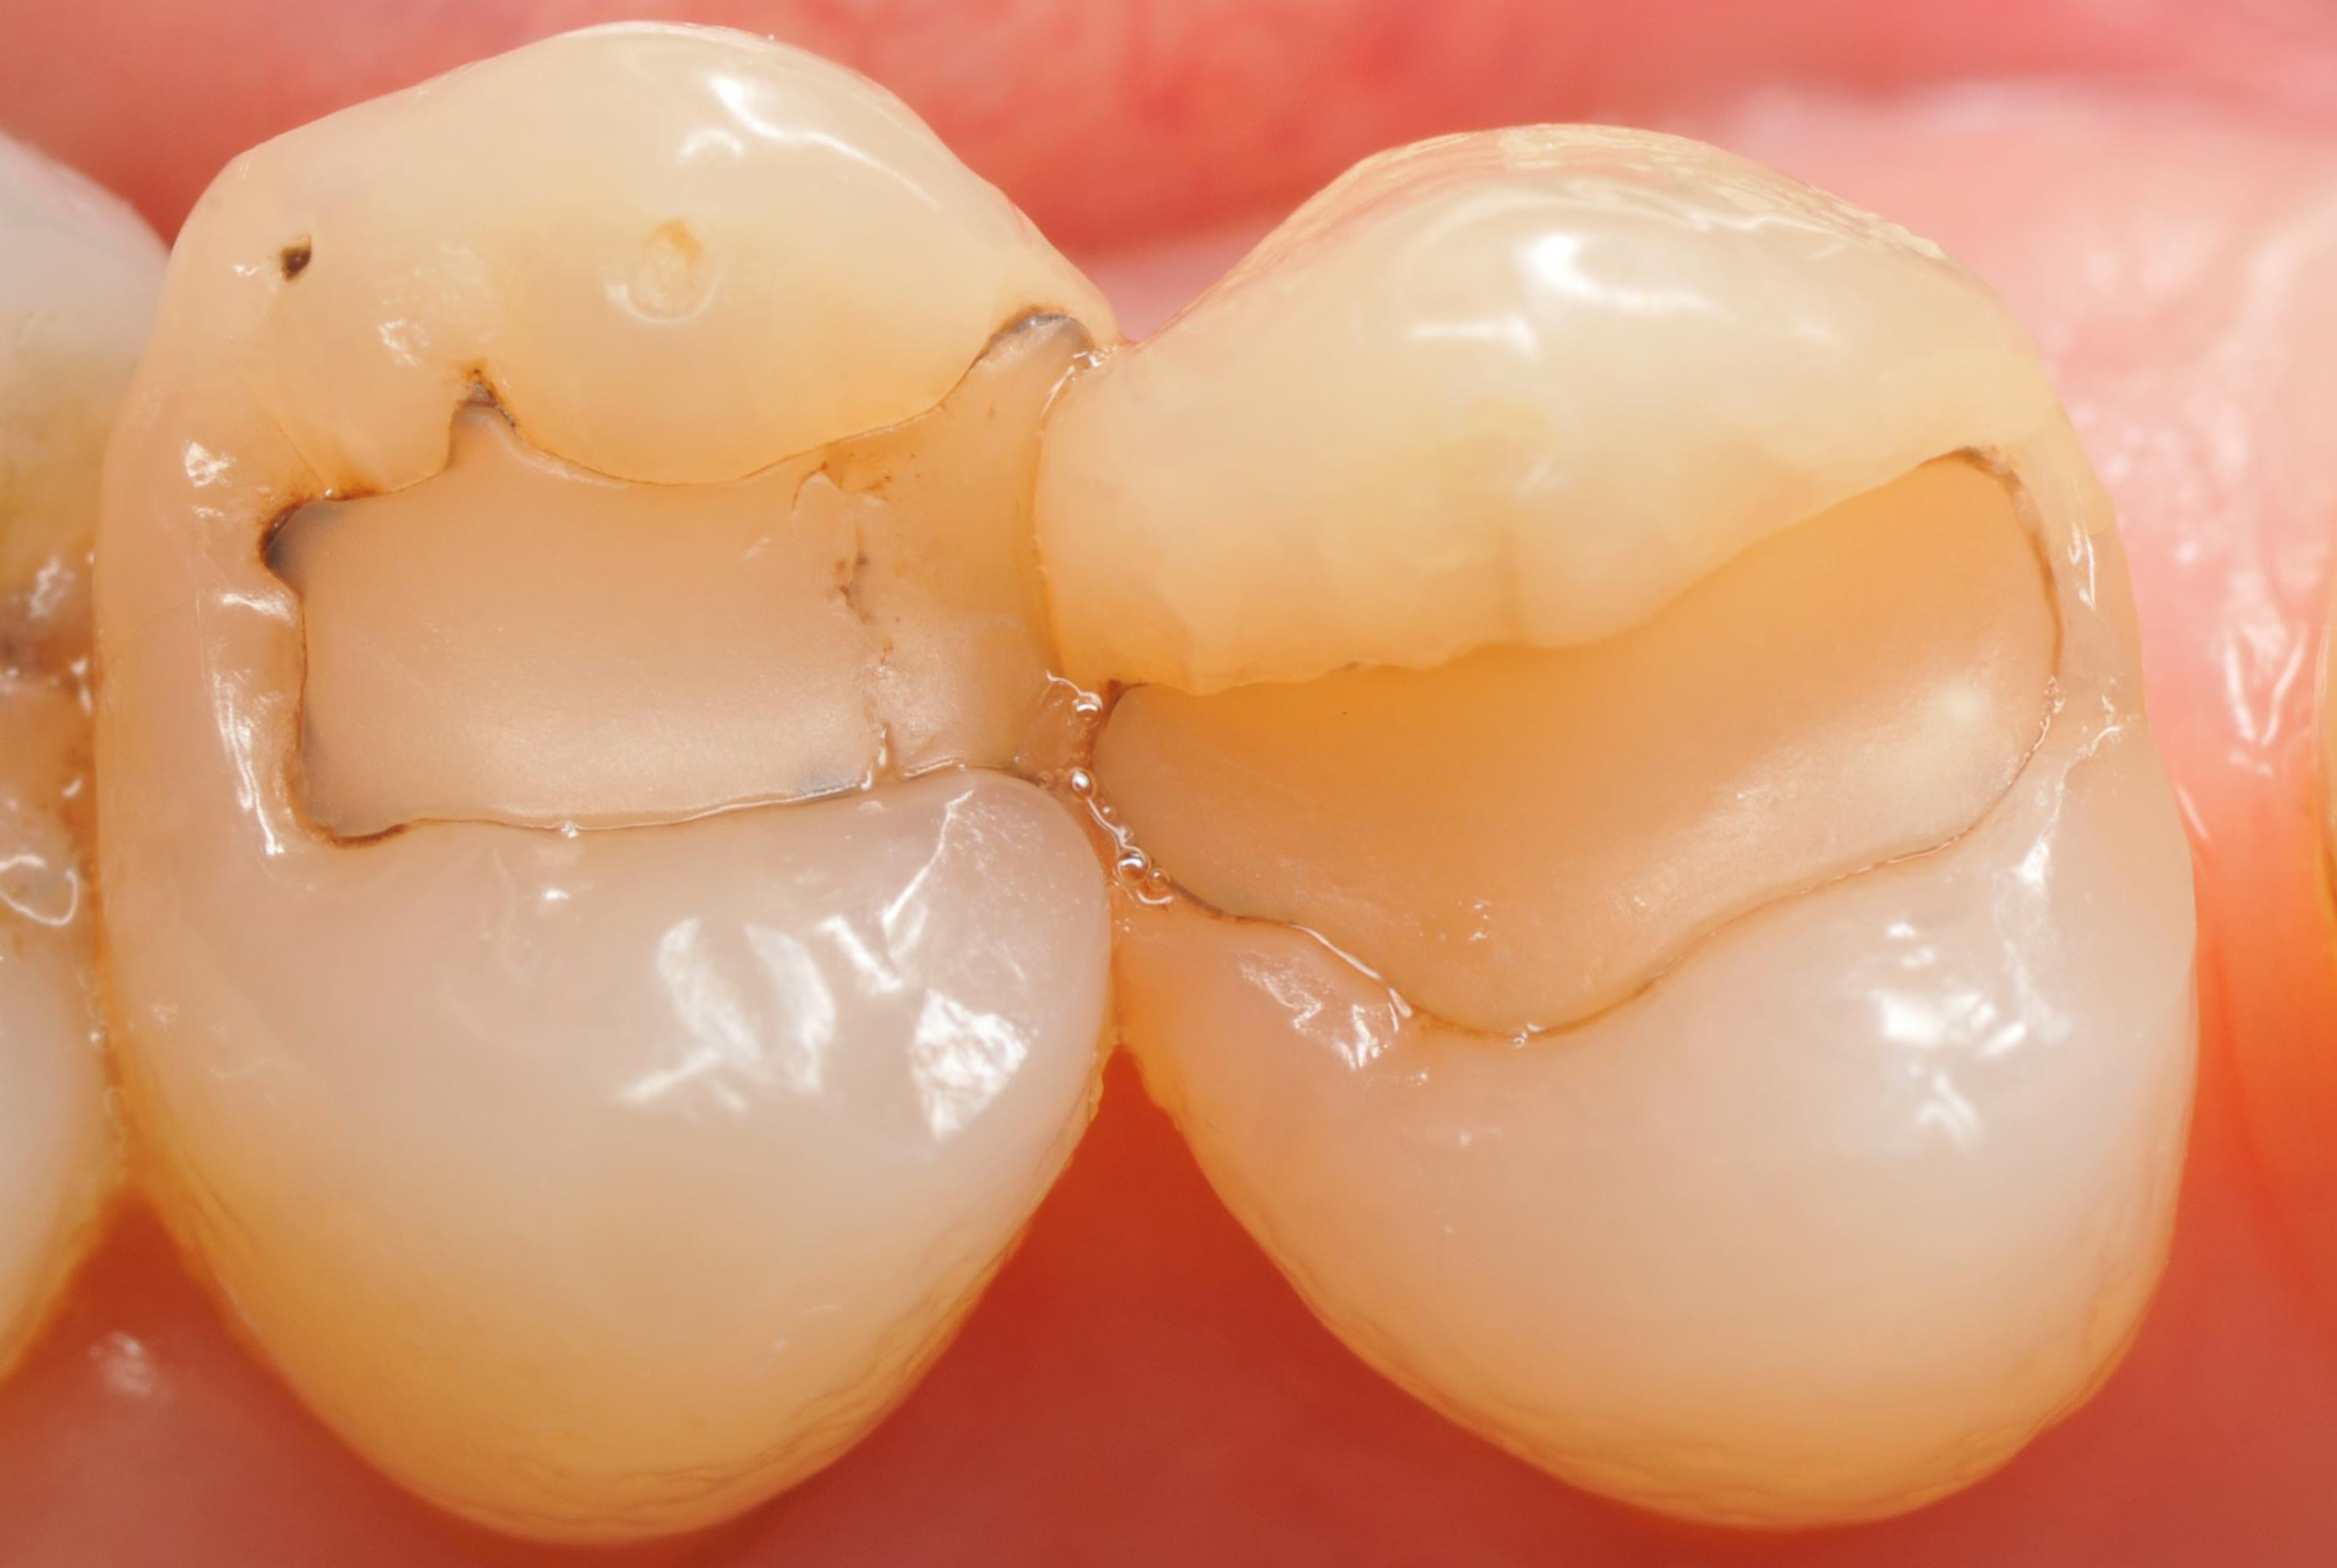

Po założeniu koferdamu usunięto stare wypełnienia i uzyskano dwa ubytki klasy II (ryc. 2).